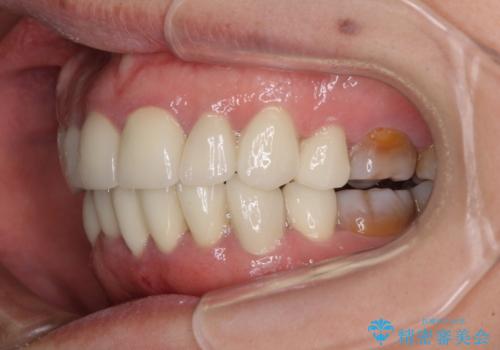

- 小さいころからの歯の変色と矯正治療の後戻りを気にして来院された患者様です。

気になる変色歯を仮歯に変え、その後歯列不正を矯正治療で改善し、最後にオールセラミッククラウンにて補綴治療することとしました。

数十年に及んだ歯の変色が改善されたため、大変満足していただきました。